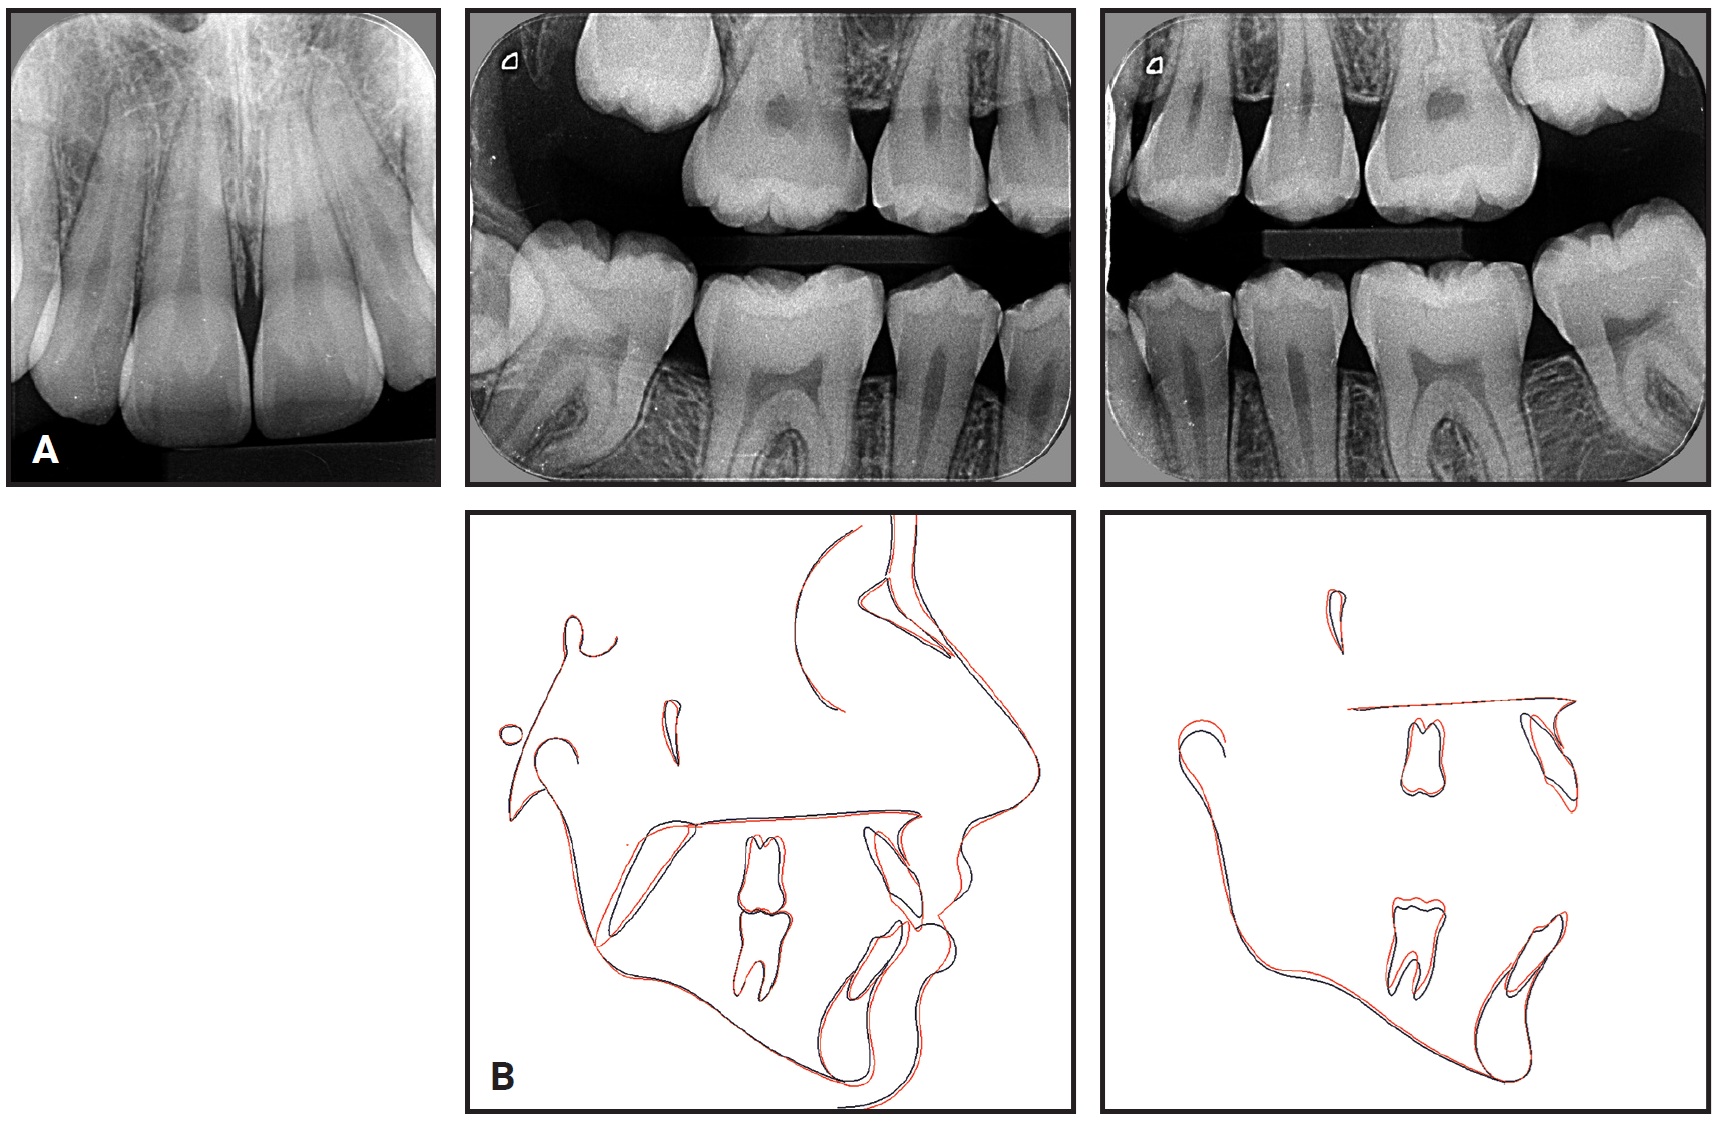

Clinical examination confirmed an anterior open bite extending from first premolar to first premolar, a bilateral Class I molar relationship, moderate lower anterior crowding, and excessive overjet. The panoramic radiograph revealed the presence of unerupted upper second and lower third molars and agenesis of the upper third molars. The upper second molars were favorably positioned for later eruption,36 with incomplete rhizogenesis (Fig. 6B). There was no deviation between centric occlusion and centric relation, and there were no signs of TMD. Cephalometric analysis found an anteroposterior maxillomandibular discrepancy with mandibular deficiency, a slightly vertical growth pattern with an excessive mandibular-plane angle, and a convex skeletal profile. The upper incisors were slightly protrusive, but the lower incisors were well positioned.

Fig. 6 (cont.) 13-year-old female patient with bilateral Class I molar relationship, anterior open bite, moderate lower anterior crowding, and excessive overjet before treatment.

Excellent smile esthetics and a static and functional occlusion were obtained. The upper incisors were extruded and palatally tipped, while the upper molars were intruded. The occlusal plane underwent clockwise rotation, and the upper posterior teeth were uprighted. Consequently, the anterior open bite was closed, the overbite was overcorrected, and occlusal contact was established between the premolars. The Class I molar relationship and the posterior transverse relationship were maintained. The lower incisors were protruded to resolve the anterior crowding. External apical root resorption involved no more than slight rounding, which is considered clinically acceptable.39 The upper second molars were erupting toward the occlusal plane, but the left second molar showed a less favorable eruption axis; therefore, the patient was kept under observation to evaluate whether surgical intervention would be required (Fig. 11B).

Fig. 11 (cont.) A. Patient after 13 months of treatment. B. Superimposition of pretreatment (black) and post-treatment (red) cephalometric tracings.